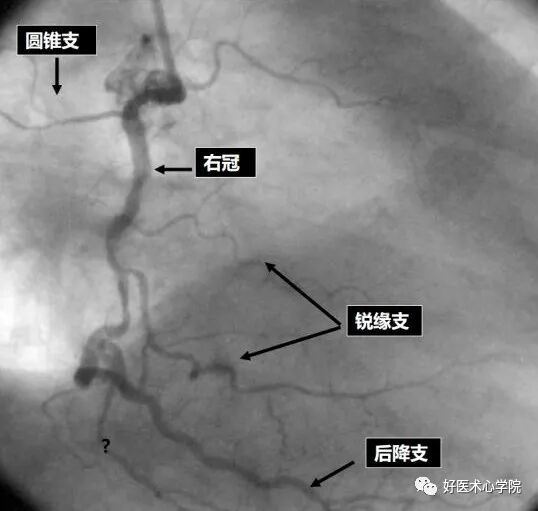

分支辨别